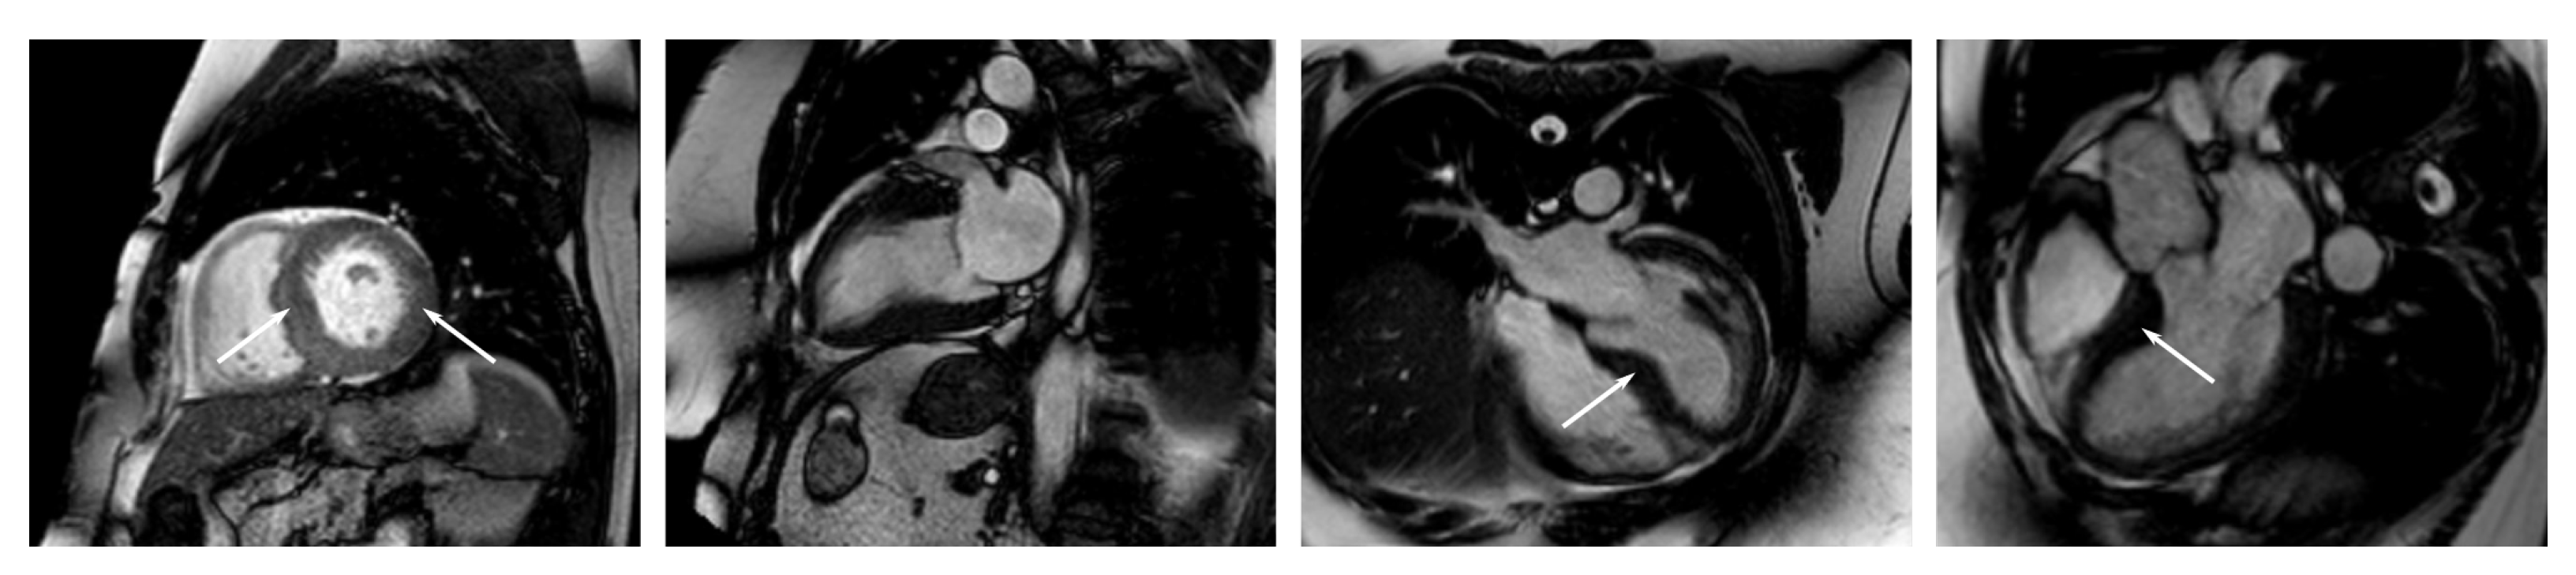

Appendix C. Example Images

- Short-axis images from the apex to the base at different stages of the cardiac cycle;

- Long-axis, two-chamber images at different stages of the cardiac cycle (heart beat);

- Long-axis, three-chamber images at different stages of the cardiac cycle;

- Long-axis, four-chamber images at different stages of the cardiac cycle.